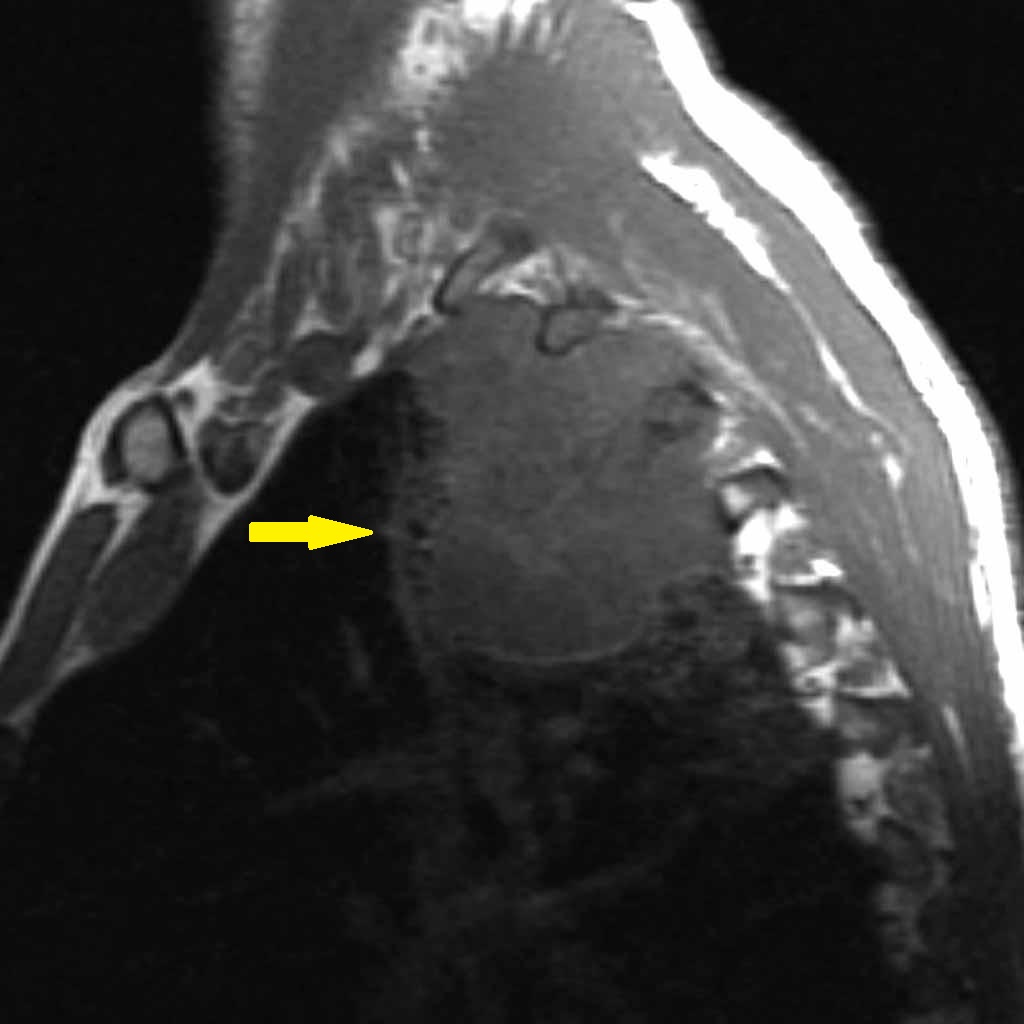

Рентгеновские снимки опухоли Панкоста